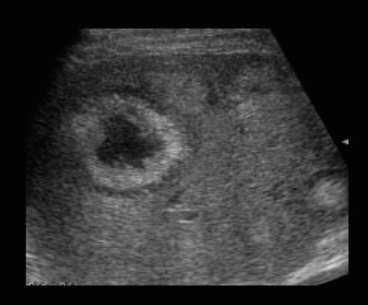

US finding

- 동일한 크기의 다발성 종괴가 나타난다.

- 고에코의 다발성 종괴: 대장암이 많으나 위암도 비교적 흔하다.

- 저에코의 다발성 종괴: 유방암, 폐암등에서 나타난다.

- 석회화나 내부 낭성 변성은 전이성 간종양을 시사하는 소견이다.

- bull's eys sign (종양 변연에 중심부가 고에코이고 경계부가 저에코인 두꺼운 띠가 보인다)

- cluster sign (종양이 융합하여 분엽모양을 이루어 마치 포도송이 모양을 나타낸다)